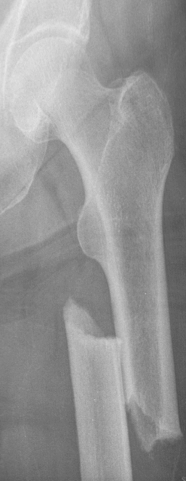

Atypical femoral fractures are rare and atypical thigh-bone fractures that have been associated with anti-osteoporosis medications that inhibit bone breakdown. The causes of these fractures are not yet known. If we can understand what factors lead to the development of these fractures, we can try to prevent them. Nevertheless, the benefits of anti-osteoporosis medications to reduce broken bones due to osteoporosis far outweigh the small risk of an atypical femur fracture.